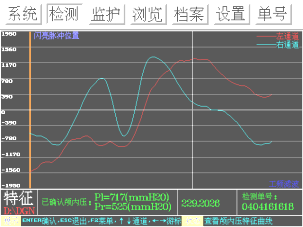

图2:双侧压力差>150mmH2O,提示脑疝趋势。

入院第1天使用重庆海威康医疗仪器有限公司无创颅内压监测仪检查患者颅内压,提示双侧颅内压增高,分别为右侧462mmH2O、左侧372 mmH2O,4h后复查右侧567mmH2O、左侧549mmH2O,第2天复查右侧525mmH2O、左侧585mmH2O,因患者临床症状好转,而无创颅内压检测提示颅内压呈持续上升状态,故引起临床重视,第3日患者症状突然加重,复查头颅CT提示“左侧颞叶大面积脑梗死,中线移位”(见图1)。此时复查无创颅内压检测:分别为右侧525mmH2O、左侧717mmH2O,双侧压力差>150mmH2O,提示脑疝可能(见图2)。之后转脑外科行手术减压治疗。起病后无创颅内压检测提示颅内压逐渐增高,并有脑疝趋势(见图3),为疾病的及时诊断提供了帮助。